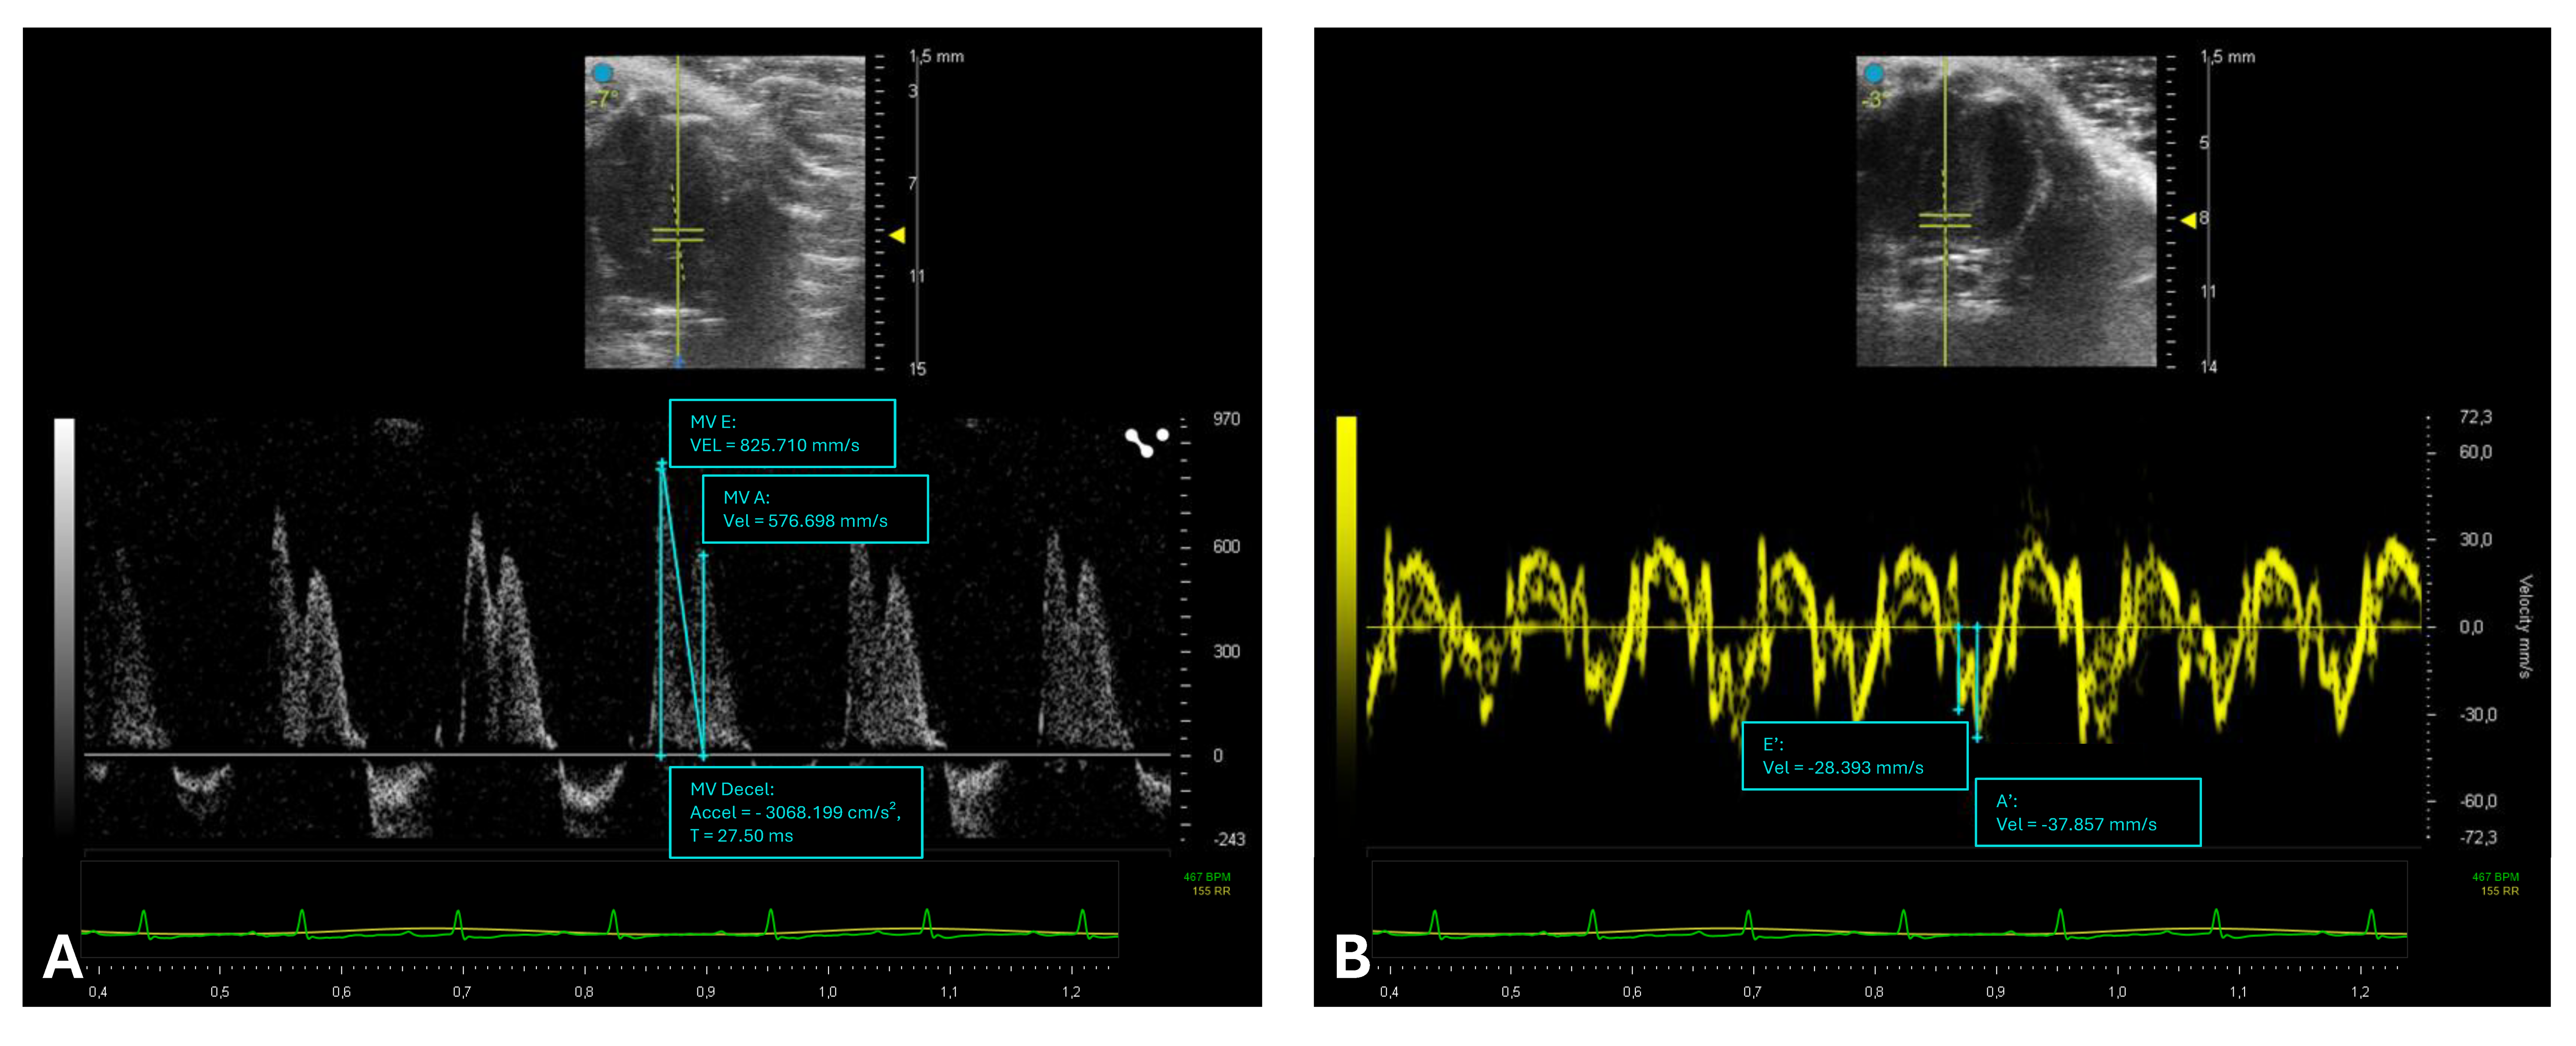

2.4. Assessment of Left Ventricular Diastolic Function